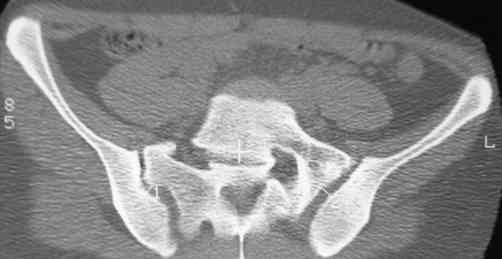

В больнице вправили вывих бедра, три недели на вытяжении. Беспокоят боли в левом тазобедренном суставе и левом крестцово-подвздошном сочленении. Ходит с тростью. Снимок - в приложении. Направил на КТ, заключение: разрыв симфиза и левого крестцово-подвздошного сочленения, переломы крыши и заднего края вертлужной впадины, горизонтальной ветви лонной кости слева.

Уважаемый д-р Булахтин, на мой взгляд единственное повреждение требующее синтеза - застарелый разрыв лона. Низкий перелом передней колонны безопасен, повреждения свода не вижу, неясно что было сзади (скорее боковая масса)лучше сделать обзорный снимок прямой и Inlet.

Очень похоже на повреждение от бокового сжатия.

Признаков разрыва сочленения не вижу, м.б. контрлатеральный перелом боковой массы.

Если был задний вывих, то повреждение должно локализоваться сзади. В данном случае перелом спереди, как результат сдавления лонного сочленения.